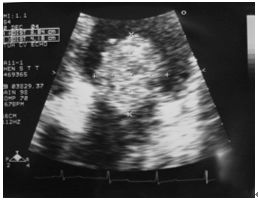

3. 病人18歲女計程車無線呼叫員, 到院主訴有五天的間 歇性燒熱及寒顫(chillness), 並合併頭痛、雙眼後疼痛及全身肌疼, 經初步診斷腦膜炎, 病人拒絕腰椎穿刺檢查, 乃試用抗生素後回家療養。 唯症狀仍舊, 尚有噁心、嘔吐, 並先後在左大拇指及右小趾出現疼痛紅斑(如圖A及B所示)。既往病史有二尖瓣膜脫垂及閉鎖不全。理學所見身高:162cm;體重:45Kg;BP:105/67mmgHg;T/P/R: 39.8C/155/18。未見Meningeal signs. 頸部末見異常, 心尖在left 5th ICS, mid-clavicular line, 有Grade III/VI Pansystolic murmur. S1及S2正常。胸、腹都無不正常。實驗室檢查: WBC:4.39x k/uL,有left shifting;RBC:5.12 x M/uL;Hb:11.0 g/dL;Platelets:130 x K/uL;其血液細菌培養結果如與胸部X光詳見附圖C、D。心電圖如附。本病人經過下列臨床處置